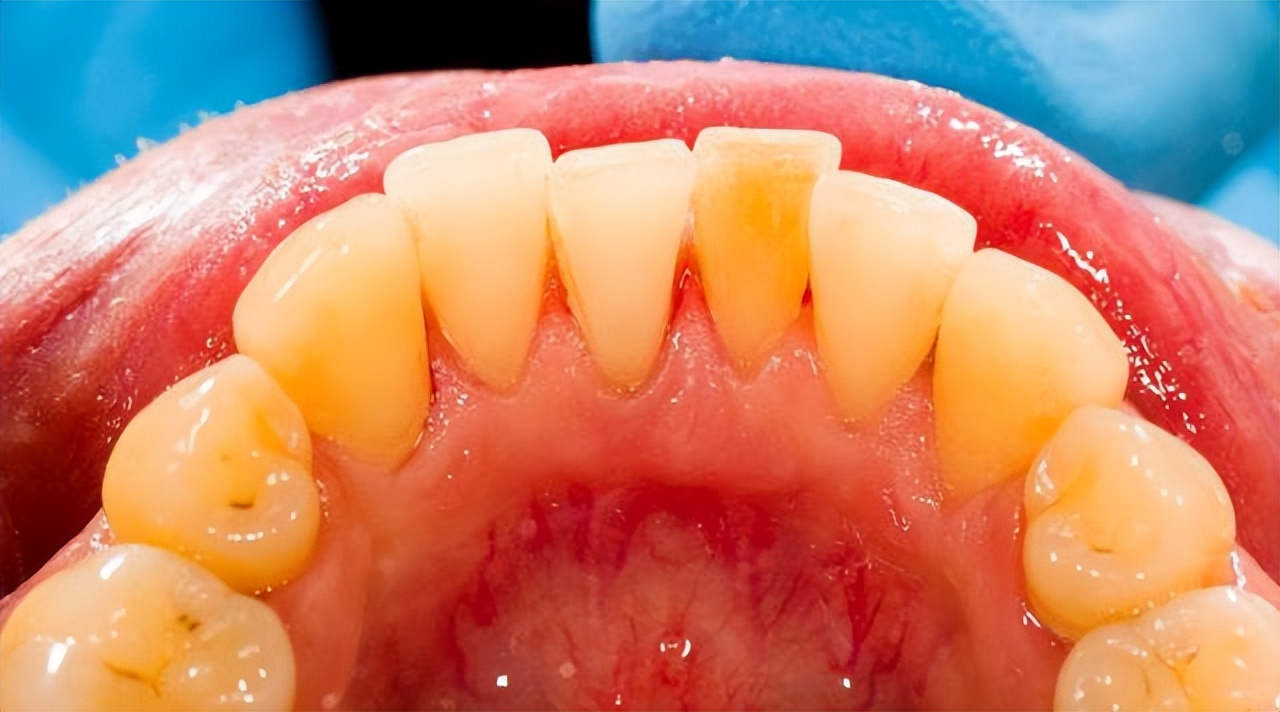

牙结石附着在牙冠或者牙齿的颈部,主要是由食物残渣物,口腔上皮细胞和唾液中的矿物质脱落和脱落形成的钙化矿物质形成。

牙结石颜色是白色或者黄色,如果吸烟会慢慢变成黑色,主要分为上牙龈结构和龈下结石。

上牙龈附着于牙齿的光滑表面,容易脱落,龈下附着于牙齿不齐的牙石,贴近穴位,不易脱落。

牙结石附着在牙齿表面是已经钙化的硬性沉积物,一般刷牙很难清除,多呈浅黄色,但常常可因饮食、喝茶、吸烟以及药物等因素导致染色加深,对牙齿美观造成了极大的不利影响。